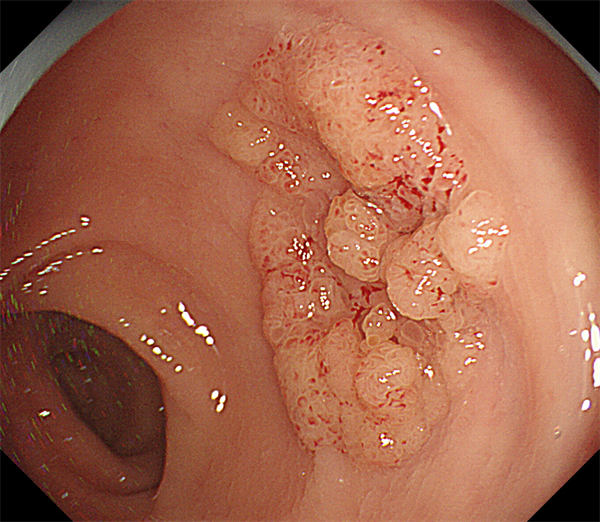

患者周某,男60岁,体检行肠镜发现直肠肿物,行肠镜下直肠黏膜下剥离术(ESD),术后病理:绒毛状管状腺瘤,局灶呈高级别上皮内瘤变。